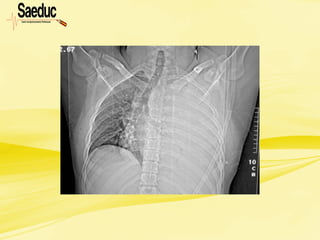

Enfisema subcutâneo

• Associado ao trauma de tórax fechado e quase

sempre há fratura de costelas com lesão da

pleura parietal e pulmão

• Passagem de ar através da solução de

continuidade estabelecida com a fáscia

endotorácica para o subcutâneo e/ou

mediastino.

• Outras causas de enfisema subcutâneo são as

lesões de traquéia, grandes brônquios e

esôfago.

• Ocorre em 20 a 25% nos casos de trauma

de tórax;

• O tamanho do enfisema não determina o

tamanho da lesão, uma vez que

pequenas lesões podem acarretar

grandes enfisemas e grandes lesões

podem acarretar pequenos enfisemas.